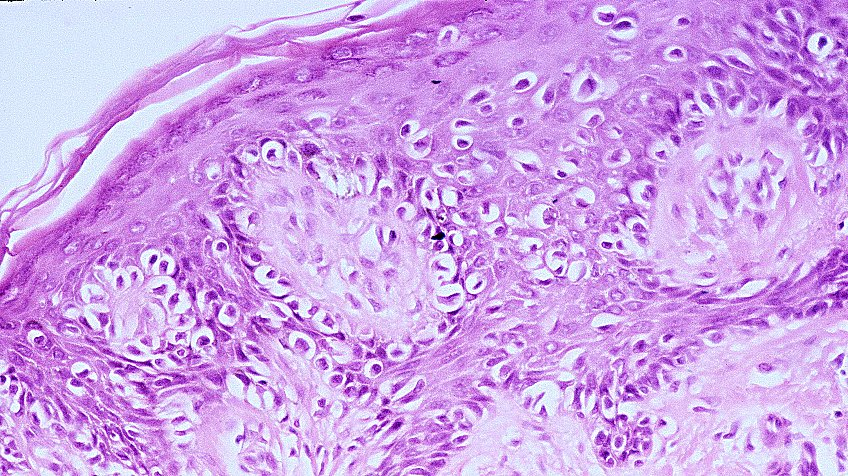

'Melanoma' is a malignant tumor derived from melanocytes (hence its denomination), neuro-ectodermal cells found in the basal layers of the skin (> 90%), mucous membranes, and the eye. Mediated through erroneus epigenetic DNA code read-outs, melanocytes transform into neoplastic melanoma cells. They proliferate and spread through soft-tissues, lymph nodes, and the blood stream, thereby turning a local tumor into a systemic disease. Untreated, melanoma is a fatal disease. Melanoma cells can be detected in histology specimens, indicated by egg-shaped clear cells displaying excentrical disconfigured cell nuclei. Intially, melanoma cells form single-cell units, followed by cluster formation. Melanin granules may be seen or even spread, but may more or less be absent in individual cases.